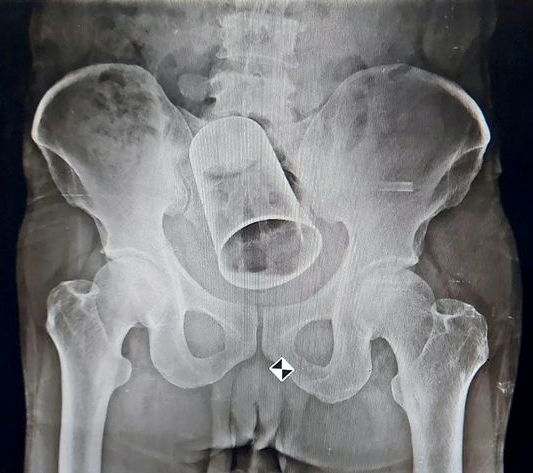

The cup, which had a diameter of 3 to 4 inches (8 cm) and a length of 6 inches (15 cm), was medically removed at a nearby hospital.

The cup was discovered to be caught in the intestine, according to an X-Ray taken at the MKCG Medical College and Hospital in Berhampur City.